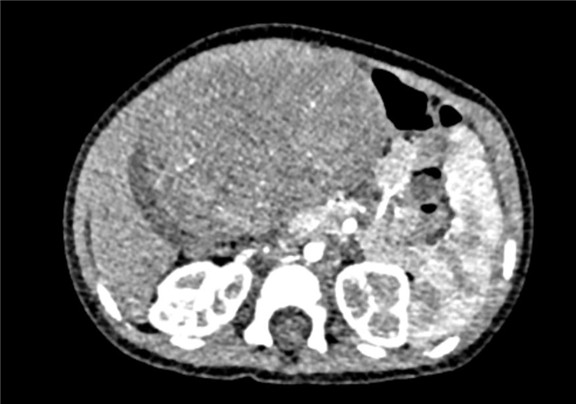

术前CT检查:

动脉期

静脉期

将0.625mm双源薄层CT资料的静脉期和动脉期Dicom格式文件导入海信CAS系统。

通过调节窗宽窗位调整CT序号,对肝实质,胆囊,下腔静脉,肿瘤,肝动脉、门静脉及肝静脉等进行三维重建;系统自动计算肝脏体积。

模拟手术操作,自动计算切除肿瘤体积。肝脏体积为310.9ml,肿瘤体积为437.7ml,肿瘤体积是肝体积的1.4倍,通过比对9-12月正常肝脏体积为321.13±118.91ml,通过术前模拟手术,精准判断切除后剩余肝脏体积能耐受,避免肝衰竭发生。